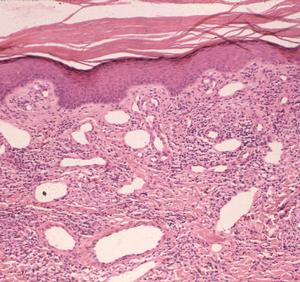

Tracing the pathophysiologic picture of non-relapsing fever Borrelia (Fig. 1) is challenging because tissue biopsies are uncommon in medical practice and the disorder isn't expected to be lethal. Thus, there are wide gaps in our knowledge of the histopathology of Lyme disease.[1] However, archived cases accumulated at referral centers, particularly in endemic regions, have added valuable information to our understanding of acute onset and long-term effects of the disease.

Figure 2

When examined by silver impregnation stain, this non-specific but suggestible infiltrate may be accompanied by spirochetes in the collagen. Rarely, the dermatitis may involve deeper vessels, even in the sub-dermal fat, which may resemble lupus erythematosus. Long-term infections have additional microvascular changes including angiopathy -- primarily occlusive changes similar to the post-capillary venulitis seen in syphilis.

Patients in Europe have been seen with a lesion of skin referred to as Borrelia lymphocytoma or lymphadenosis benigna cutis, usually involving the ear lobe, lateral neck skin, or areola of the nipple. The histology is instantly recognizable by a marked dermal infiltrate of lymphocytes and other mononuclear inflammatory cells totally, or nearly totally replacing the dermis, with well-formed germinal centers (Fig. 3), as seen in lymph nodes or tonsillar lymphoid tissue, hence the term lymphadenosis. This is a remarkable lesion clinically and pathologically and is not always caused by Borrelia infection. When it is, however, the clinician should look for the spirochetes, which can be seen by silver stains. Other examples of early disseminated infection, which may be seen days to weeks following tick bite, include meningitis, radiculoneuritis, encephalopathy and Bell's palsy.

Figure 3